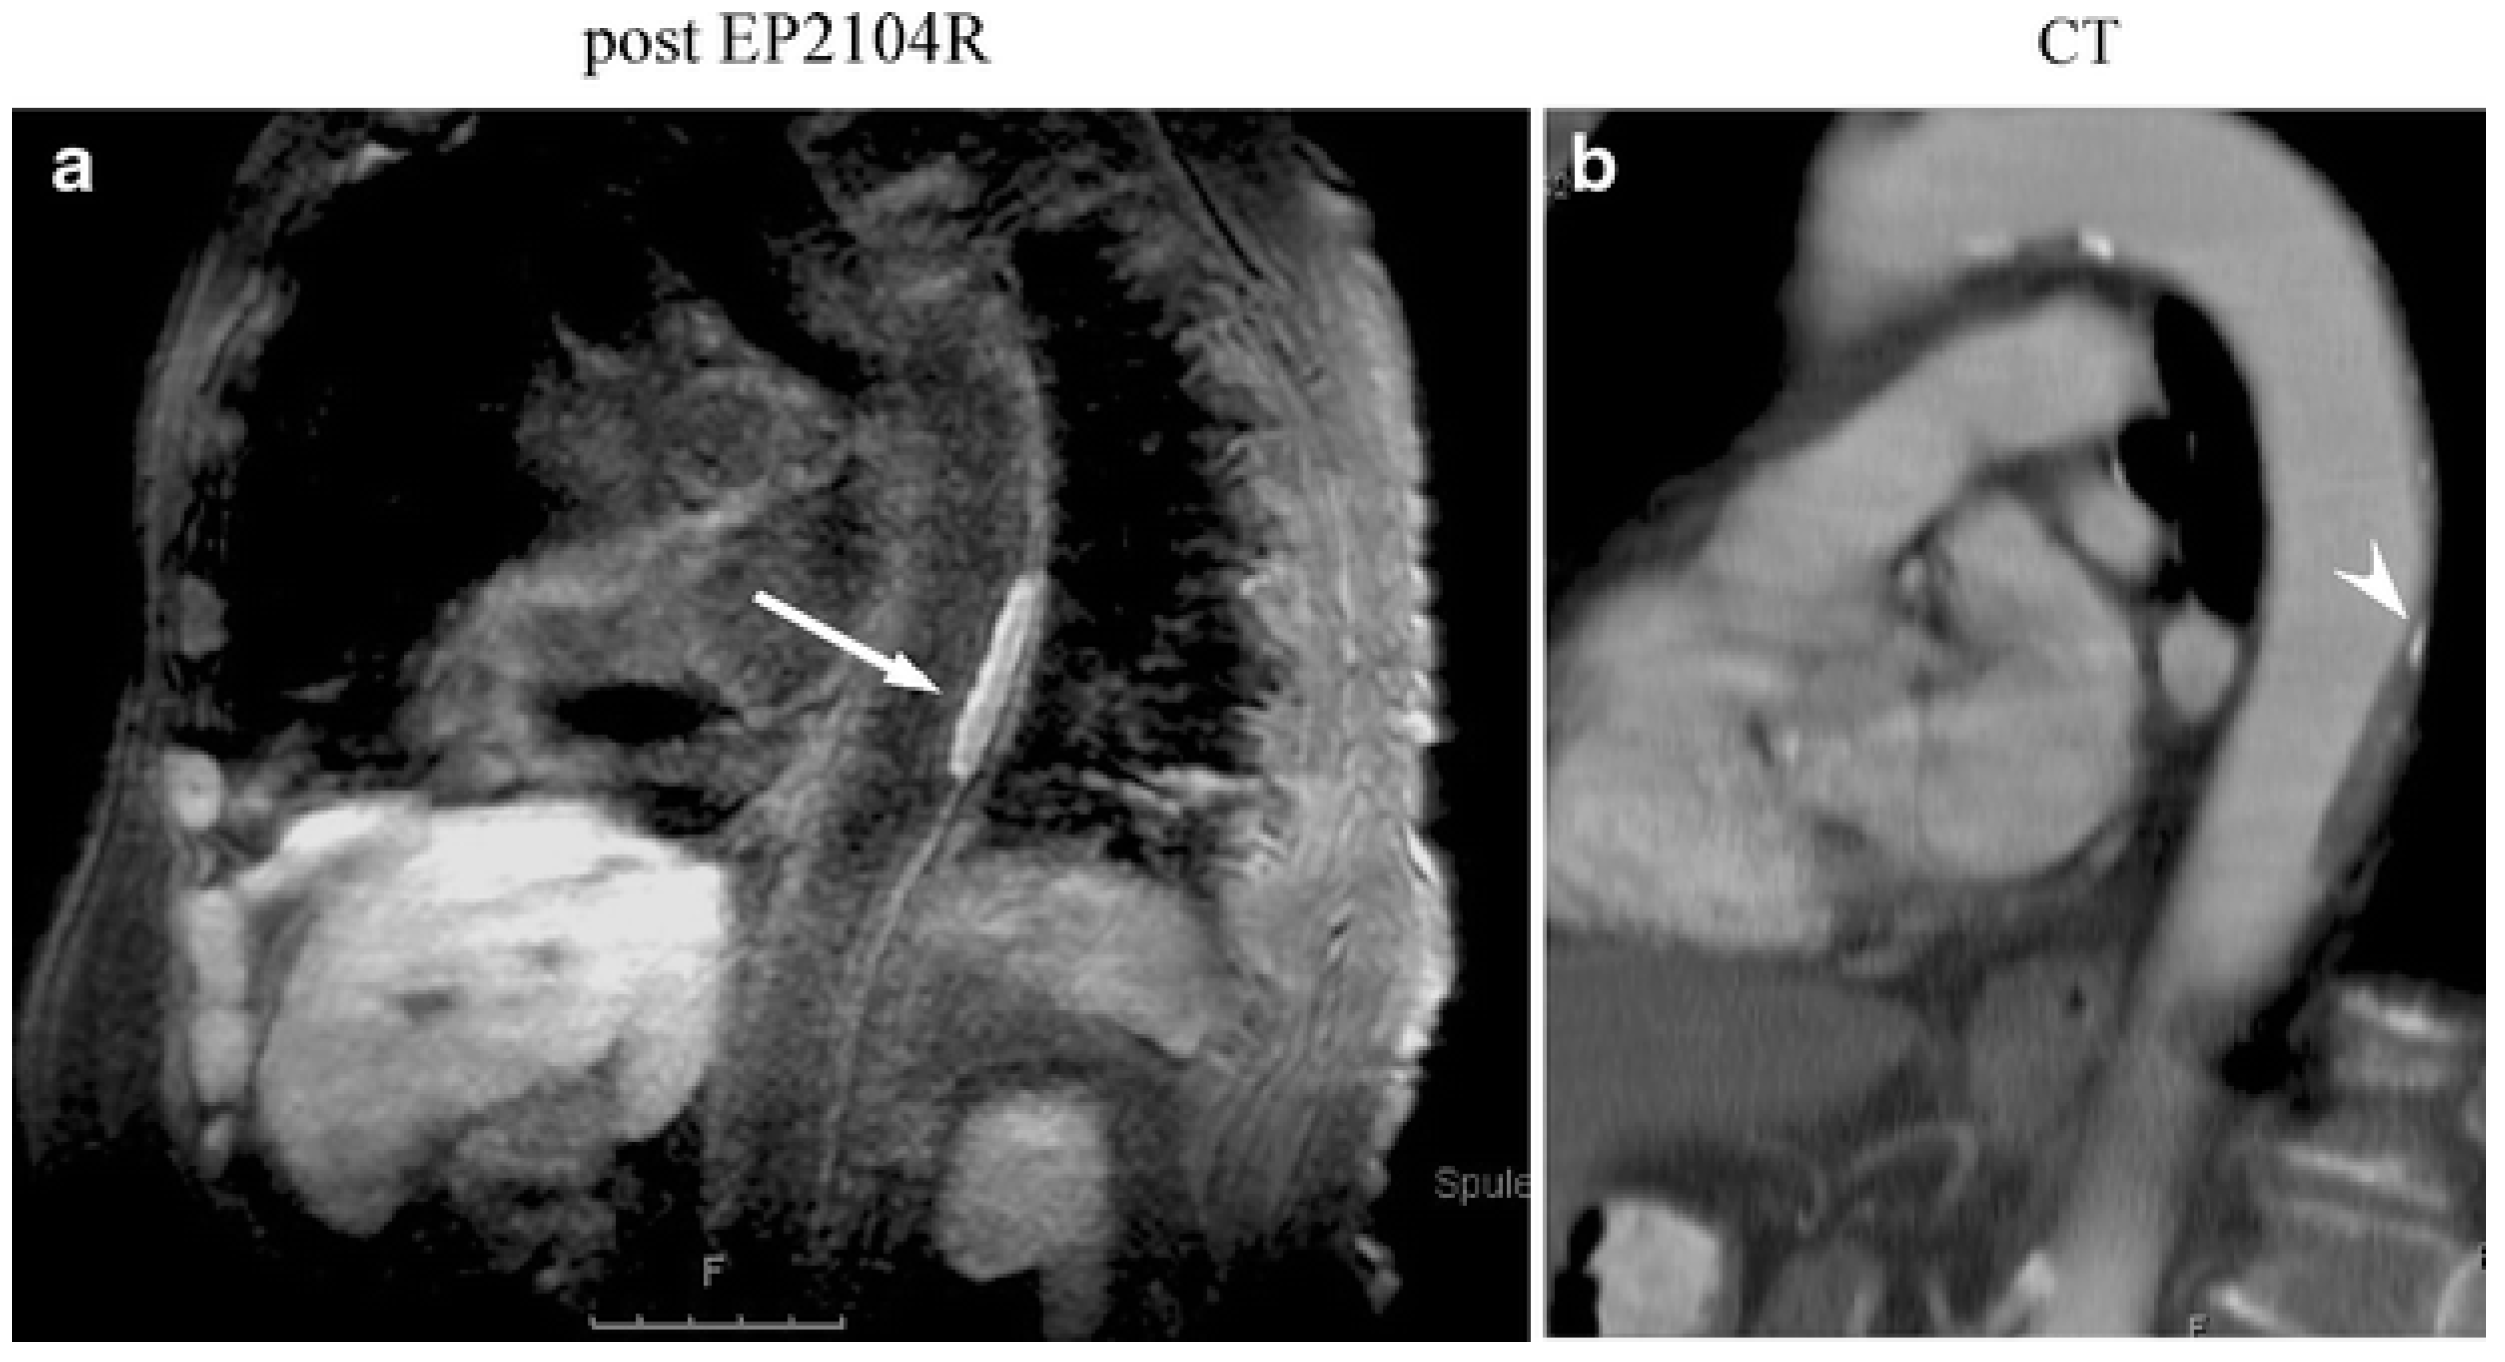

- Botnar, R.M.; Wiethoff, A.J.; Ebersberger, U.; Lacerda, S.; Blume, U.; Warley, A.; Jansen, C.H.P.; Onthank, D.C.; Cesati, R.R.; Razavi, R.; et al. In vivo assessment of aortic aneurysm wall integrity using elastin-specific molecular magnetic resonance imaging. Circ. Cardiovasc. Imaging 2014, 7, 679–689. [Google Scholar] [CrossRef]

- Botnar, R.M.; Brangsch, J.; Reimann, C.; Janssen, C.H.P.; Razavi, R.; Hamm, B.; Makowski, M.R. In Vivo Molecular Characterization of Abdominal Aortic Aneurysms Using Fibrin-Specific Magnetic Resonance Imaging. J. Am. Heart Assoc. 2018, 7, e007909. [Google Scholar] [CrossRef]